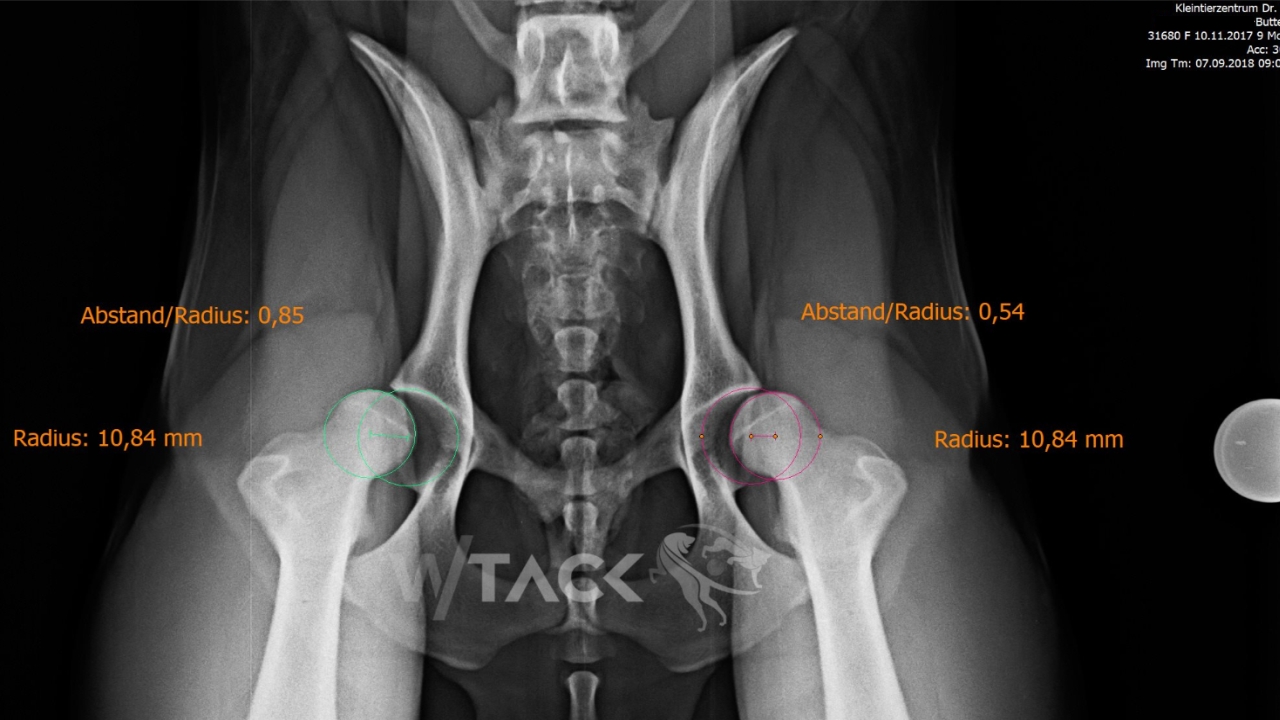

Buttercup – Goldendoodle, 10 Monate, w, 24kg Wegen beidseitiger Hüftgelenksdysplasie führten wir gestern eine beidseitige Pfannenschwenkung (DPO rechts 30°, DPO links 25°) durch.